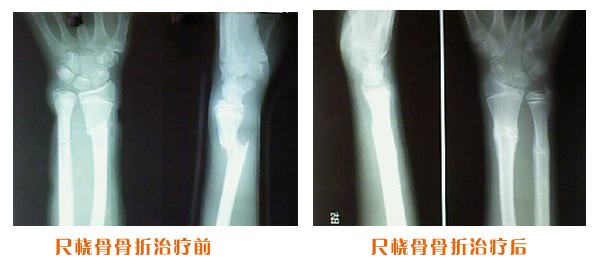

尺橈骨骨折治療前后

尺橈骨克雷氏骨折治療前后